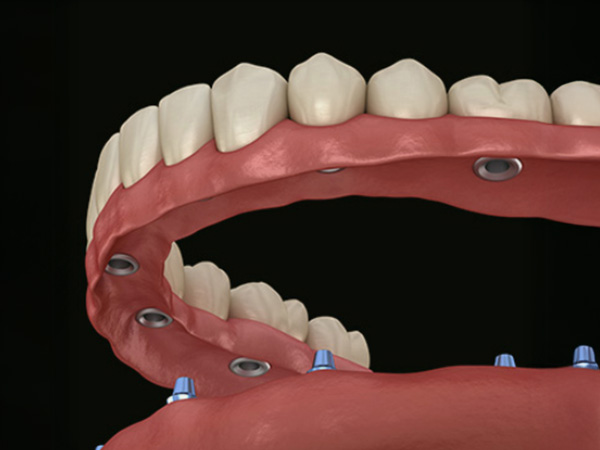

무절개 임플란트틀니는 잇몸을 크게 절개하지 않고, 잇몸 표면에 작은 구멍을 내어 임플란트 고정체를 심은 뒤 그 위에 틀니가 단단히 연결되도록 설계하는 치료입니다. 이 방법은 기존 틀니에 비해 잘 빠지지 않고 덜 흔들려, 식사나 대화 시 안정감 있는 사용을 돕는 것을 목표로 합니다.

잇몸을 넓게 여는 수술에 비해 시술 시간이 짧고 부기와 통증이 적어 고령의 환자분이나 전신질환이 있는 분들도 비교적 부담을 줄이고 치료를 계획하실 수 있습니다. 충분한 검사와 상담을 통해 잇몸 뼈 상태를 확인한 후 개인별로 임플란트 개수와 위치를 조절해, 일상생활에 무리가 적도록 기능과 편안함을 함께 고려하여 진행합니다.

최소식립 전악임플란트는 칼로 잇몸을 절개하는 방법이 아닌 임플란트 식립 부분만 작은 홈으로 구멍을 뚫어 시술하는 방법입니다. 이 치료 방법은 수술 후 통증이나 붓기, 출혈이 거의 없어 부담이 없는 수술입니다.

기존의 절개 수술에 비해 수술 시간이 짧고 병원 내원 횟수가 적어 연세가 많으신 고령의 환자 또는 당뇨와 고혈압 같은 전신 질환이 있으신 분들도 안전하게 시술하실 수 있어 최고의 정확성과 안정성을 보장하며 부작용을 최소화합니다.